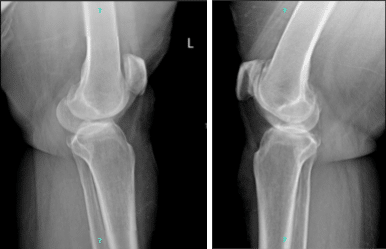

The patient also brought and presented X-Ray results for both of her knees. For the left, there are mild osteoarthritic degenerative changes. There are no acute fractures. However, for the right, there are moderate osteoarthritic degenerative changes. Joint effusion. There are no fractures.

Left and right knee x-ray complete patella